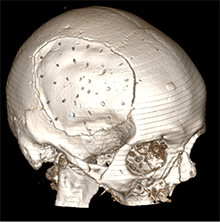

6 pav. Perforacijos KPL

Dėl anksčiau gydytų EDS, susidariusių atlikus KP, klinikinėje praktikoje KPL buvo atlikta daugybinių perforacijų. Mokslinės literatūros duomenimis, KPL, turinčio fenestracijų, daug geresnės išeitys negu KPL, neturinčio fenestracijų [11], nes EPS susisiekia su subgaliniu tarpu ir dėl slėgių gradiento rezorbuojasi į minkštuosius audinius. Per padarytas skylutes EDS susisiekia su subgaliniu tarpu, seroma labiau kaupiasi po minkštaisiais audiniais negu epiduraliai. Nustatyta, kad aponeurozei būdinga gera rezorbcija, todėl EDS linkusios regresuoti [12].

Straipsnyje aptariamu atveju paciento KPL skirtinas mažiausiai (75 cm2) grupei, kuriai būdinga minimali infekcijos atsiradimo rizika (13 pav.), tačiau operacijos metu vis tiek buvo paimtas mikrobiologinis pasėlis infekcijai ekskliuduoti. Mokslinėje literatūroje taip pat pristatomas siekis tirti skirtingų pirminių galvos smegenų hematomų, po kurių reikėjo atlikti kraniektomiją, koreliaciją su EDS, tačiau reikšmingų rezultatų negauta [8].